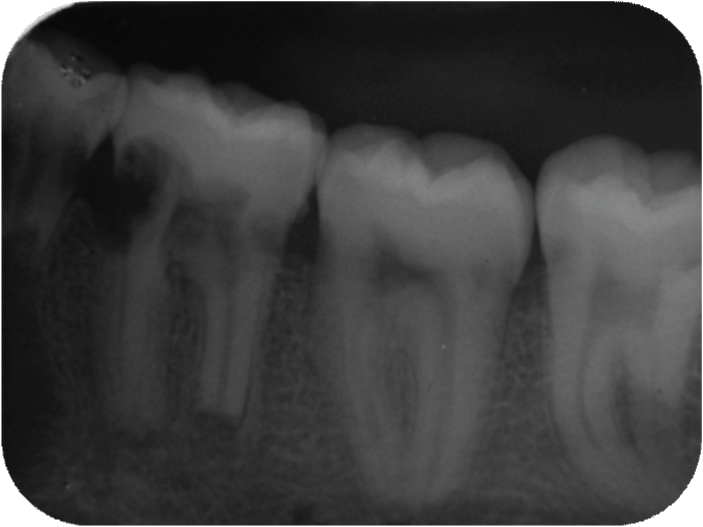

In [Table/Fig-8] intraoral periapical radiograph showing cervical resorption in relation to 33, 34, resorption in both cervical and apical region in relation to 35, 36. In [Table/Fig-9] intraoral periapical radiograph showing cervical and apical resorption in relation to 24, 25 and apical resorption in relation to 26. In [Table/Fig-10] intraoral periapical radiograph showing cervical and apical resorption in relation to 35, 36 and apical resorption in relation to 37. In [Table/Fig-11] intraoral periapical radiograph showing cervical and apical resorption in relation to 46, 47 and 48. In [Table/Fig-12] intraoral periapical radiograph showing cervical resorption in relation to 43, 44 and 45. [Table/Fig-13] Orthopantomograph. In [Table/Fig-14] lateral view of skull showing no osteogenic changes. In [Table/Fig-15] histological examination of extracted mobile teeth showing striae of Retzius, dentinal tubules and interglobular dentin with an area resembling dead tract. Correlating the history, clinical findings supported by radiographic appearance, diagnosis of Multiple Idiopathic external root resorption was made.

Intraoral periapical radiograph showing cervical and apical resorption in relation to 46, 47 and 48